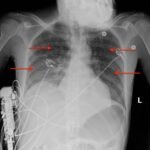

This is a case report of an HIV-positive patient with miliary tuberculosis (MTB). He presents to the emergency department (ED) two-weeks following the initiation of antiretroviral therapy (ART) with worsening cough, fevers, and malaise. The patient was diagnosed with Tuberculosis-Immune Reconstitution Inflammatory Syndrome (TB-IRIS) and subsequently treated with corticosteroids, resulting in clinical improvement over a two-week in-patient hospitalization. This case report details a rare case of TB-IRIS, a clinical diagnosis without universally agreed upon criteria. It also demonstrates a classic miliary pattern of disseminated tuberculosis on chest radiography.